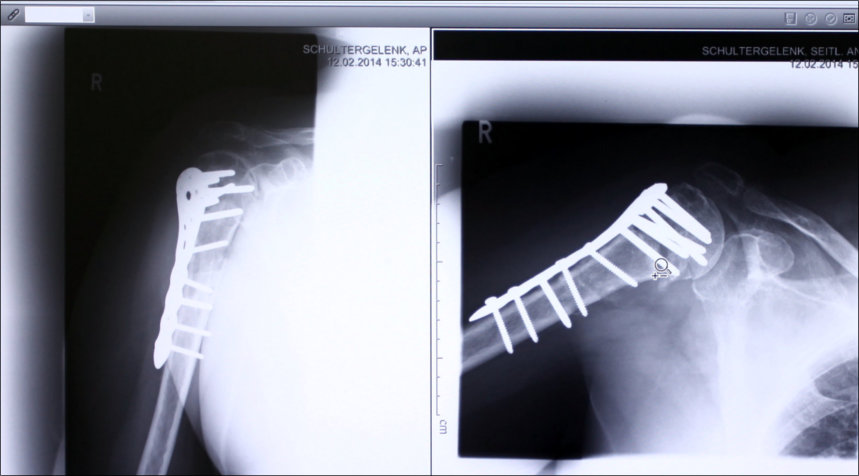

Digital Röntgen

Die digitale Röntgenanlage ermöglicht eine

hochauflösende exakte bildgebende Diagnostik

unter den Sicherheitskautelen des Strahlenschutzes.

Röntgenbefunde können digital archiviert und unter

Verwendung der digitalen Medien weitergeleitet

werden.